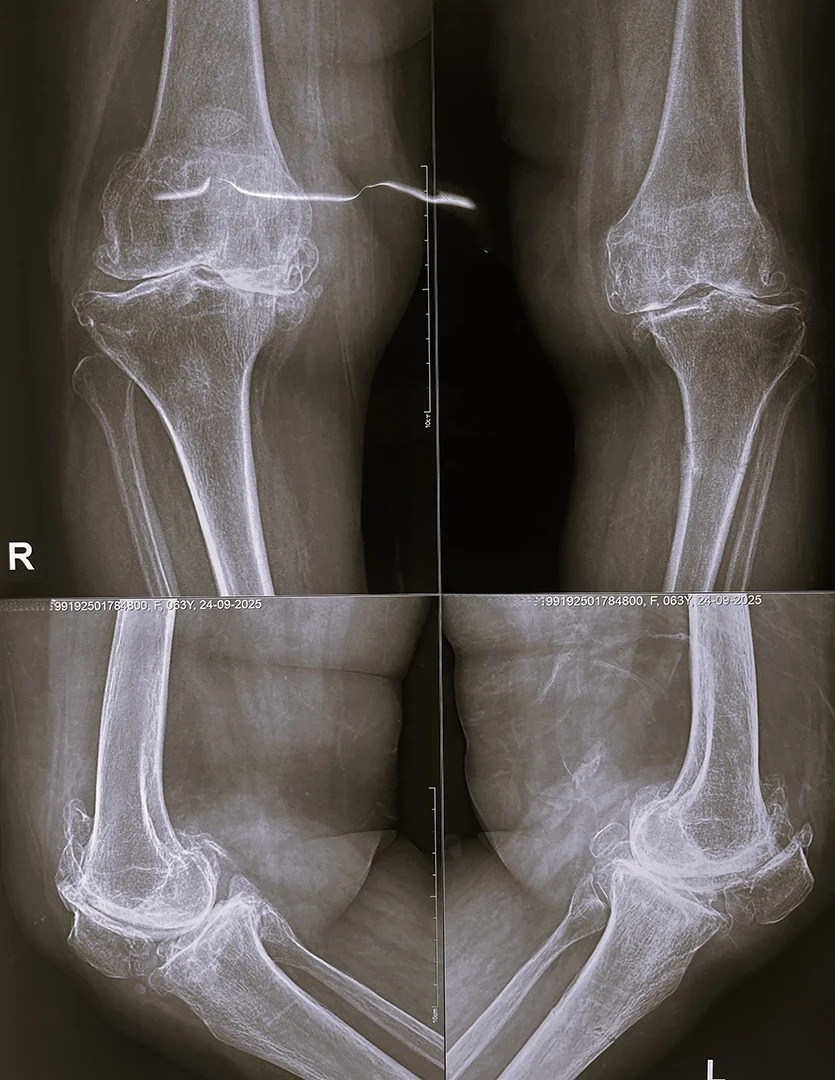

Stress Fracture of Tibia with Rigid Varus Deformity

Pre-Op X-Ray